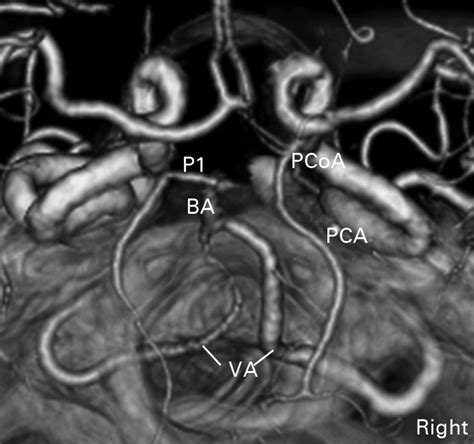

The Posterior Communicating Artery typically originates from the posterior aspect of the internal carotid artery, just before it bifurcates into the middle and anterior cerebral arteries. From this origin, the artery courses posteriorly and medially to join the posterior cerebral artery (PCA). The presence and size of the PCoA can vary significantly among individuals; while it is usually a delicate vessel, in some cases, it can be quite prominent, particularly if the PCoA serves as the primary supplier of blood to the posterior cerebral artery—a condition known as a "fetal-type" posterior cerebral artery.

The anatomy is characterized by several key features:

• Connectivity: It serves as the physical link between the anterior circulation (carotid system) and the posterior circulation (vertebrobasilar system).

• Size Variability: Its diameter can range from very thin, almost thread-like structures to robust vessels that appear almost as a continuation of the internal carotid artery.

• Branching: It provides essential perforating branches that supply deep brain structures, including the hypothalamus, thalamus, and the subthalamic region.